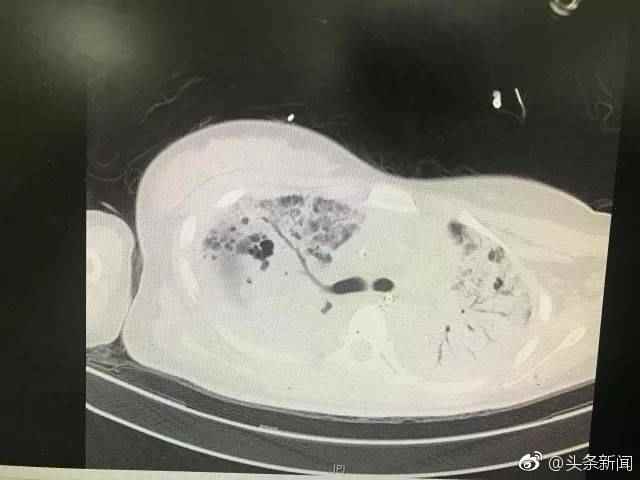

1月初,20岁的小文全身酸痛乏力、发烧,以为只是感冒。因高烧不退,她到医院就诊,随后被转入ICU治疗。原来她感染了名叫MRSA的“超级细菌”,48小时生存率仅63%。经过21天的治疗,小文平稳,预计一周后可以出院。